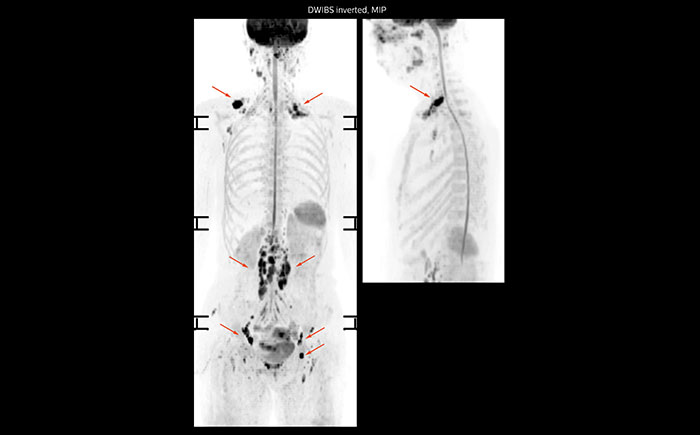

Whole body diffusion

A 61-year-old female with a malignant lymphoma underwent an MRI exam with whole body diffusion weighted imaging (DWIBS) as well as PET. On the images shown, the resolution of DWIBS is better than PET, which allows visualization of the small pelvic lesions and almost no distortion is seen in the neck area.

MR neurography of nerve sheath lesion

This patient is a 43-year-old female with a left supraclavicular nerve sheath tumor. The lesion is well visualized on the STIR VISTA images and on the MR neurography using DWIBS. The exam was performed on Prodiva 1.5T.

MR neurography using DWIBS inverted, full MIP

Acq voxel size 1.2 x 1.3 x 2.4 mm, Recon voxel size 0.7 x 0.7 x 1.2 mm, dS SENSE factor 2, scan time 5:46 min.